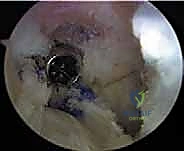

- الجراحة المجهرية وتنظير المفاصل بدقة 4K: يستخدم الدكتور هطيف أحدث تقنيات مناظير الركبة (Arthroscopy) المزودة بكاميرات عالية الدقة 4K، مما يتيح له رؤية أدق التفاصيل داخل المفصل، وتشخيص الأضرار المجهرية، وإجراء الجراحة بأقل تدخل جراحي ممكن (Minimally Invasive).

* الأشعة المقطعية (CT Scan): في حالات الفشل الجراحي، تعتبر الأشعة المقطعية السلاح الأهم. فهي توفر نمذجة ثلاثية الأبعاد (3D) دقيقة جداً لمواقع الأنفاق العظمية القديمة وحجمها، مما يساعد الدكتور هطيف في اتخاذ قرار حاسم: هل يمكن حفر أنفاق جديدة فوراً، أم يجب إجراء الجراحة على مرحلتين؟